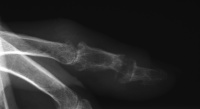

| Late result. Lateral tophi

have progressed. |

| The joint has remodelled

further, but there is painless functional motion. |